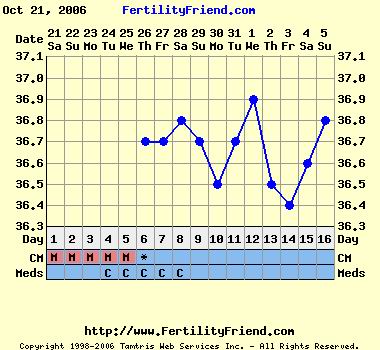

Kíváncsian várom a görbéd folytatását, szerintem most lesz PÉ-d!